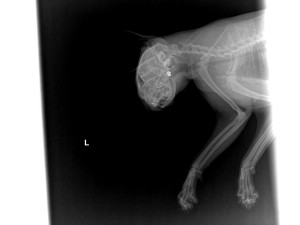

Dosud neznámý tyran střelil v obci Vícemilice na Vyškovsku kočku zblízka do hlavy. Zvířeti hrozí trvalé následky, může oslepnout. Do rány na čumáku se jí dostaly kovové kousky kulky a v tlamě se jí udělal hematom. V útulku, který o ni momentálně pečuje, odmítá žrát. Pachateli hrozí až šest let za mřížemi. Charitativní kočičí spolek Kryšpín nabízí celekm pětadvacet tisíc tomu, jehož svědectví povede k odhalení tyrana.

Hrůzný případ se odehrál v polovině května ve Vícemilicích na ulici Družstevní. Do zdejšího útulku se dostala vážně raněná kočka. Někdo ji zblízka střelil do hlavy. Postřelené zvíře do útulku přinesla žena, která v okolí pečuje o toulavé kočky. Mourince hrozí trvalé následky. Na jedno oko neviděla už předtím, nyní zásluhou malé kulky může ztratit zrak úplně.

Diabolka trefila zvíře v místě, odkud ji veterináři nedokážou vyjmout. „Při bližším ohledání je viditelné popálení kůže a chlupů kolem rány, dráha poranění s mnohočetnými kovovými fragmenty a hematom v tlamě na tvrdém patře. Přední končetiny jsou pokryté zaschlou krví. Oteklá je pravá tvář a oko. Levé oko je atrofované, zapadlé a nefunkční, kočka je apatická a nepřijímá potravu,“ uvedl v lékařské zprávě Marek Blaško působící právě v Útulku Tibet.